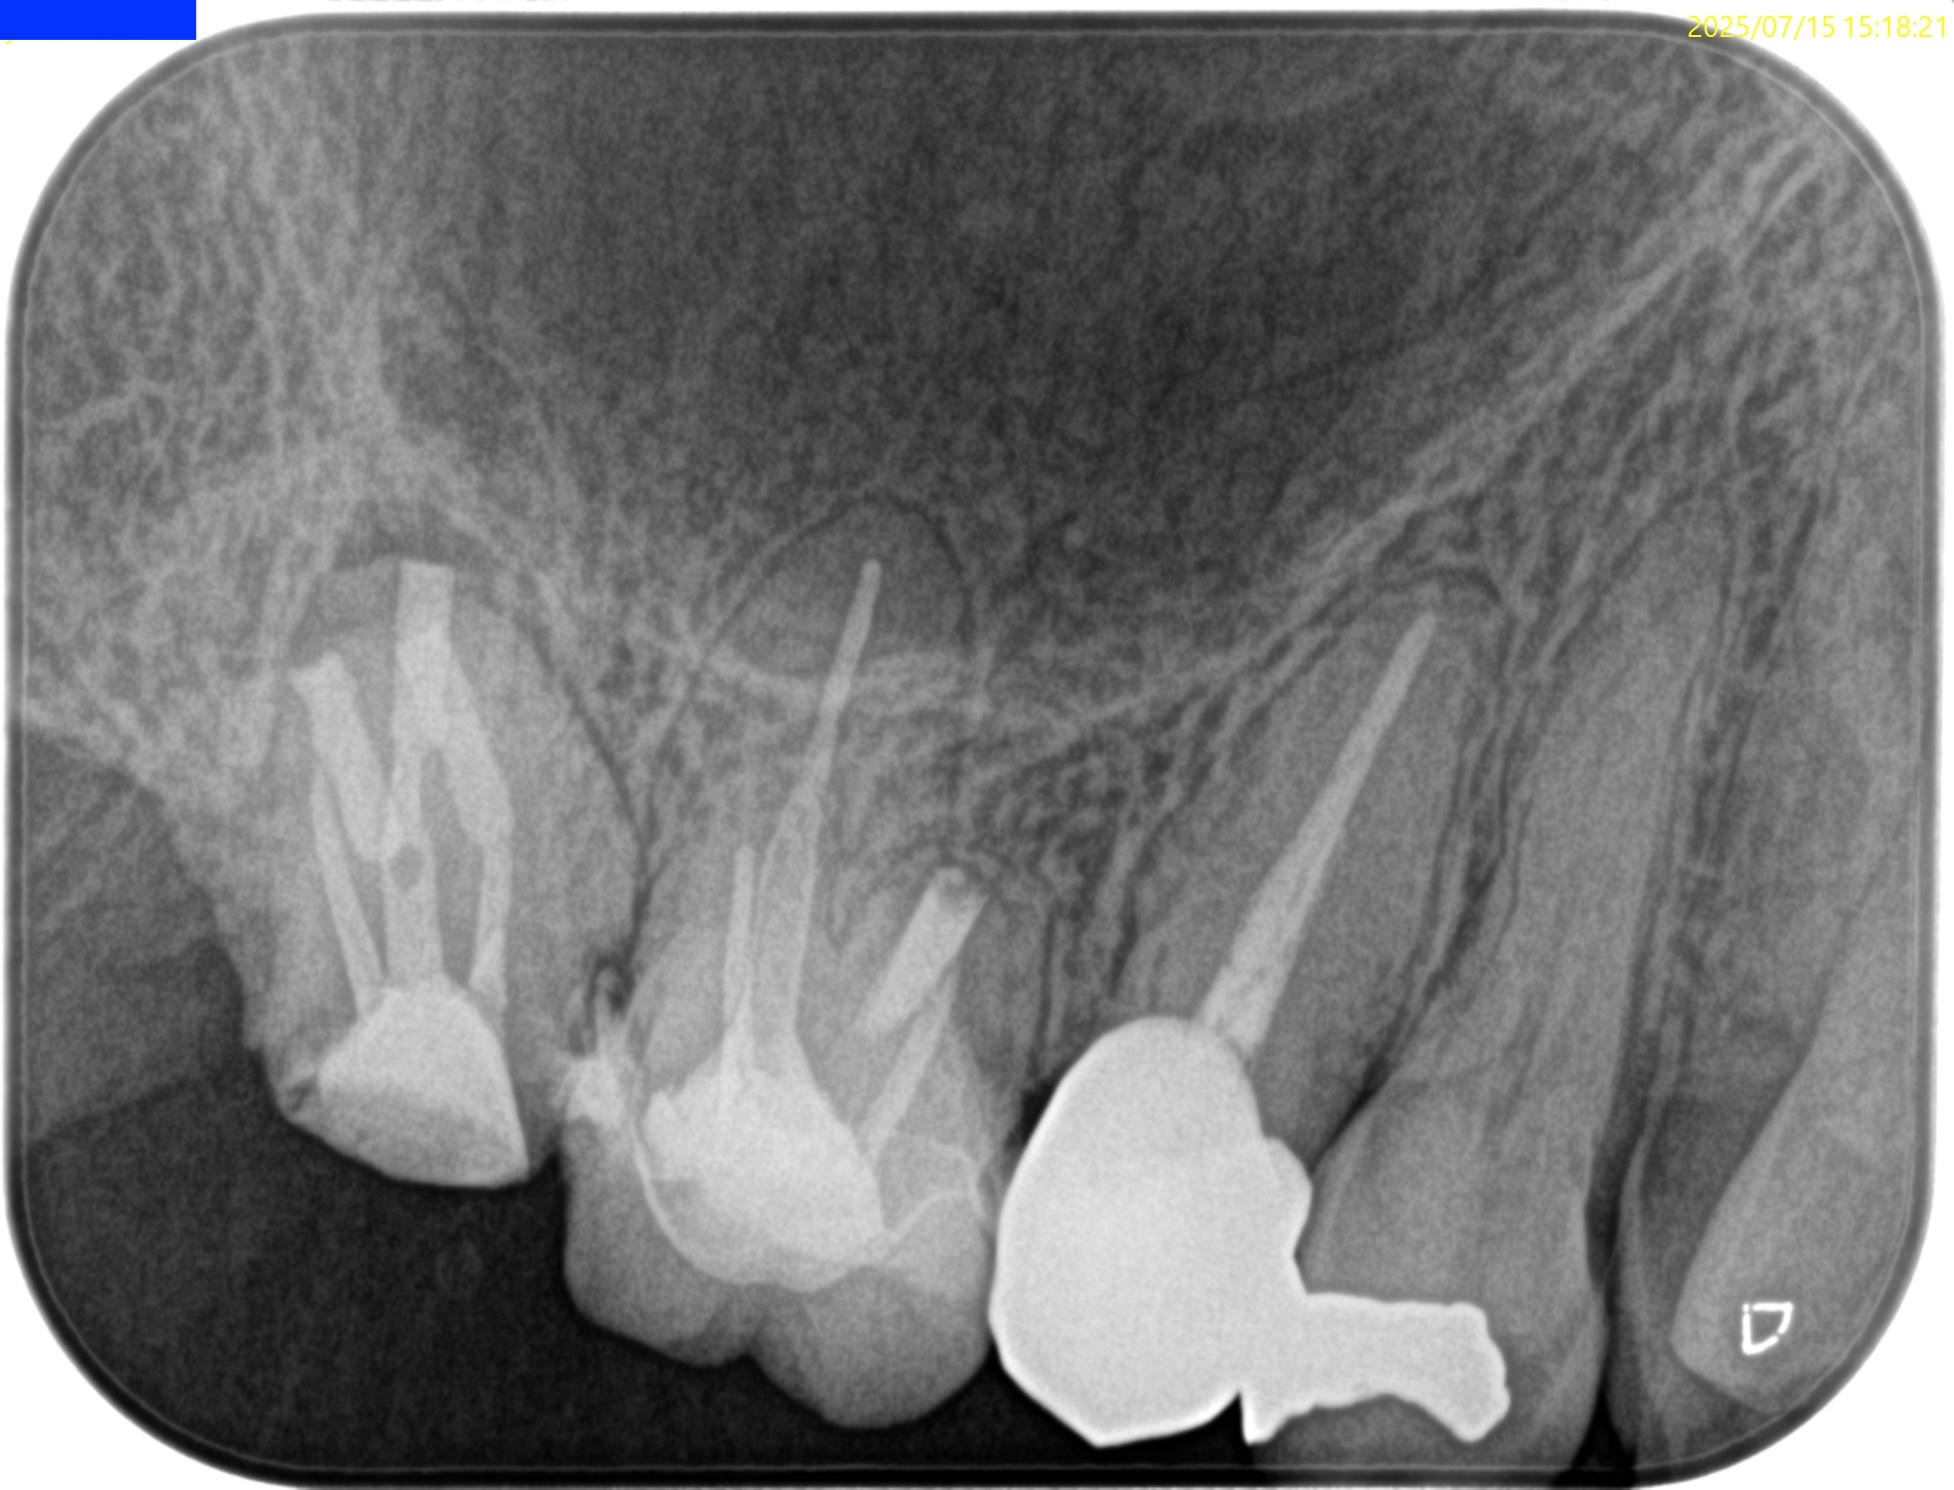

歯内療法学的検査(2025.7.15)

石灰化が進行し穿通が厳しい。

MB,DB,Pと全ての根管は石灰化している。

さらに悪いことには根尖病変がある。

歯内療法学的診断(2025.7.15)

Pulp Dx: Previously treated

Peiapical Dx: Symptomatic apical periodontitis

Recommended Tx: Core build up→Intentional Replantation